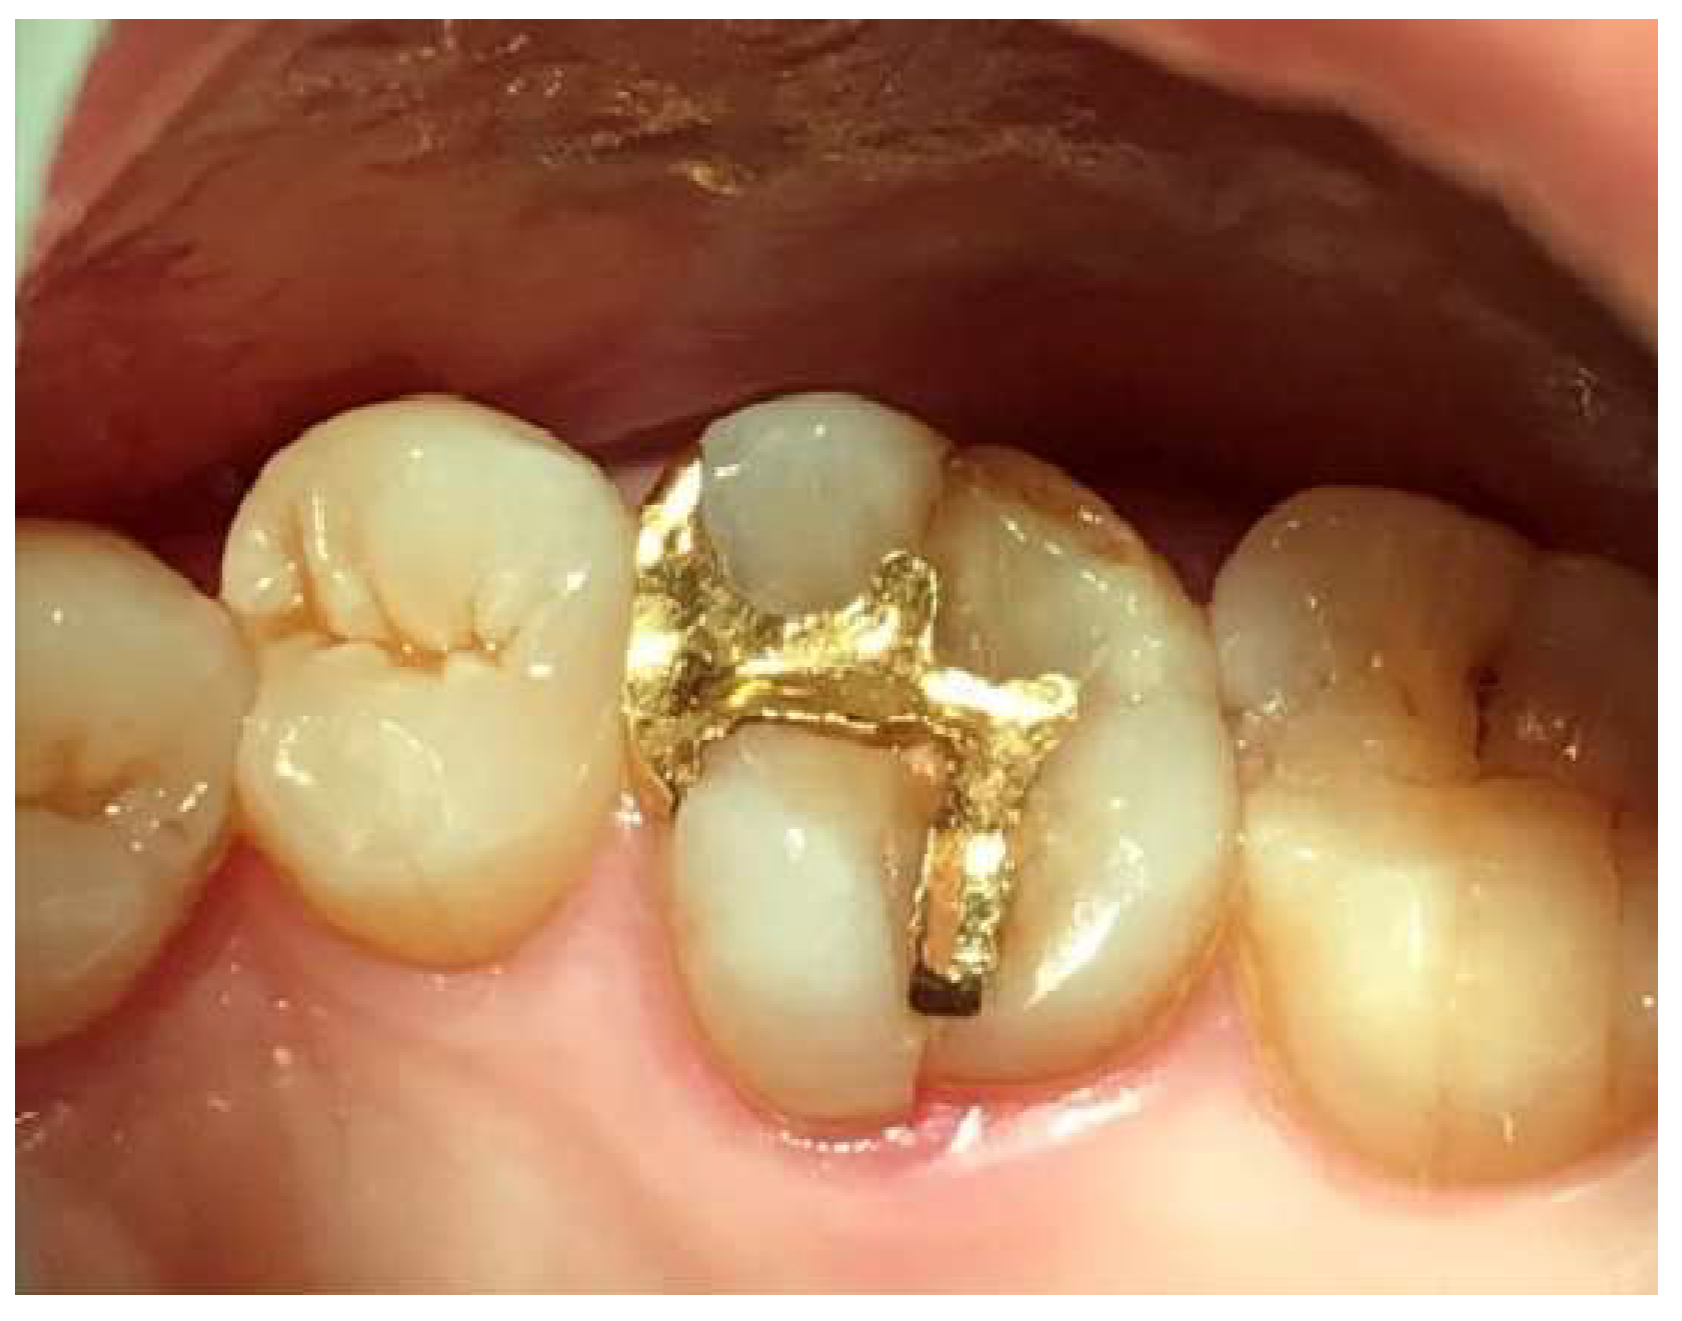

Following the restoration remake, the patient reported no further discomfort, including gingival bleeding, swelling, or food impaction. Clinical examination confirmed healthy peri-implant soft tissue with no radiographic bone resorption. Probing with the Implant Paper Point Probe (IPPP) (Sure Endo, Seoul, South Korea) at a yield strength of 0.35 N showed a consistent depth of less than 1 mm, with no bleeding, confirming the successful resolution of peri-implant mucositis.

Figure 6 compares the restorations before and after revision, highlighting profile differences. It also includes a post-revision panoramic X-ray and clinical photographs taken on October 31, 2022 (

Figure 6).

Figure 6.

The upper left image presents a comparison of the two restorations before and after the revision, while the upper right image shows a panoramic X-ray taken post-revision. The lower two images display the clinical appearance of the upper left first molar implant restoration following the revision procedure conducted on October 31, 2022.

Figure 9.

Clinical images of control and experimental sites post-revision. This figure presents clinical photographs of the control and experimental implant sites following the revision procedure. Both sites exhibit a natural and healthy appearance, indicating successful soft tissue adaptation and restoration aesthetics, taken at 2024.